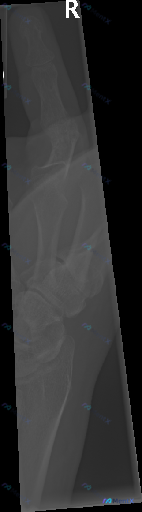

这张手指侧位X光报了"未见明显异常",但用户明确说存在异常,你会怎么考虑?

整理了一份影像读片的讨论材料,有点意思,也有点陷阱。 基础情况: - 影像:右手指(可能是拇指)侧位X光片,视野偏局限,主要显示近节指骨、掌指关节区和部分掌骨头 - 原始影像报告描述:骨皮质连续,骨小梁清晰,掌指关节对位良好,关节间隙均匀,未见明显骨折、脱位、骨质破坏或高密度异物 - 关键前提:这份...